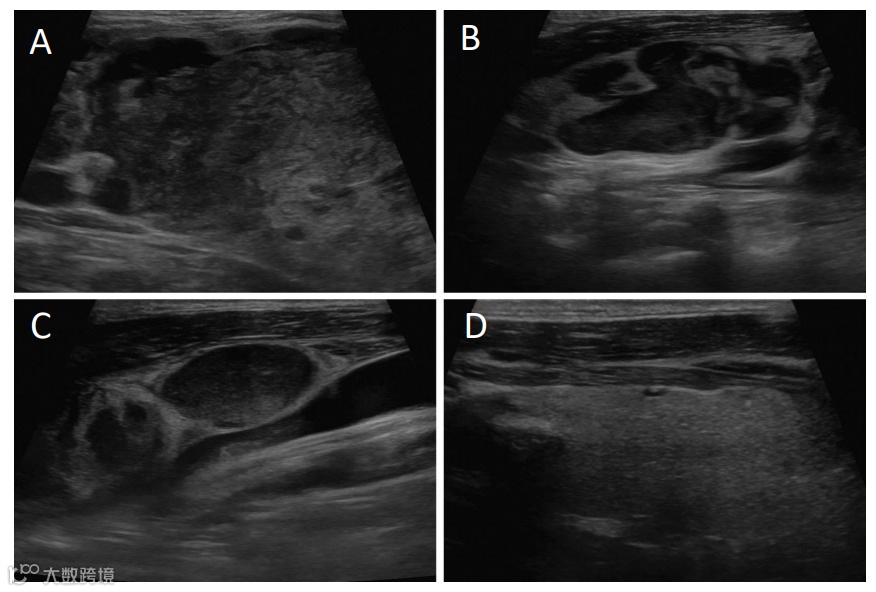

腹部CT显示肝脏肿块增大,淋巴结呈现弥漫性病变,并发现多处骨性病变。颈部超声检查发现右侧颈部淋巴结异常肿大,右侧甲状腺有一个5.3 cm大小的异质性肿块占位(图1),进行淋巴结活检,结果证实为转移性肝细胞癌(图2)。

(A)甲状腺右叶伴有异质性肿块;(B)颈部右侧第3级淋巴结形态异常病变;(C)颈部右侧第3级和第4级淋巴结形态异常病变;(D)左侧甲状腺叶正常外观